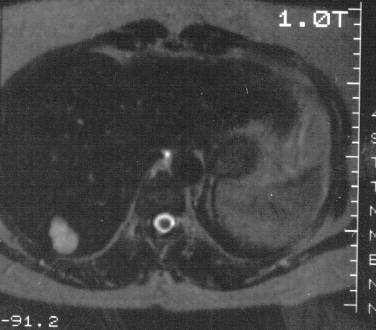

Paraarterial or subcapsular localisation, central thrombosis or fibrosis may interfere with the safety of diagnostic evaluation. In this case, MRI can be performed which is very sensitive to hemangiomas (size under 0,5 cm is also indicated – figure 21).

Figure 21: Hemangioma in the liver, T2 weighted MRI

Hemangiomas appear as a bit lower signal intense lesions compared to the liver parenchyma on the T1-weighted images.

A very high signal intensity can be observed on T2-weighted images. T2 relaxation time fluctuation (the strength of signal intensity by T2) is affected mainly by the extent of thrombosis/fibrosis.

Dynamic contrast MR study can be also performed, which demonstrates the slowed flow dynamics of the hemangioma (similarly to CT): haemangiomas fill up from outside inward as an iris or wheelspoke form in case of typical appearence.